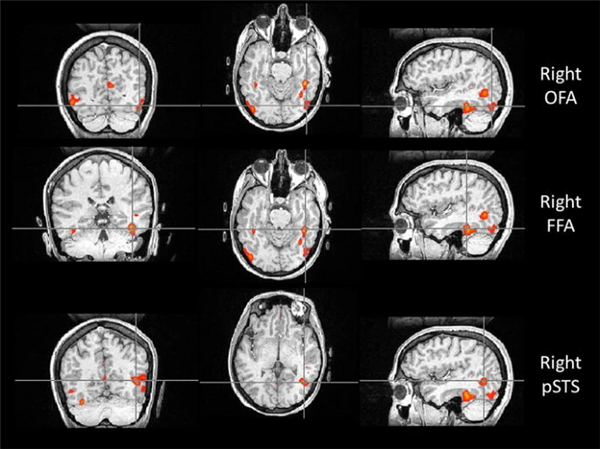

比如,位于枕叶的枕叶面孔区(Occipital Face Area, OFA),就像识脸网络的“先锋部队”。它专门处理眼睛、鼻子和嘴巴等五官“零部件”。当一张脸出现在我们眼前时,OFA 只需 约 100 毫秒 就能被激活,迅速对局部特征进行拆解,并将信息传递给 FFA 和上颞沟(Superior Temporal Sulcus, STS)。所以如果 OFA 出现问题,识别人脸就会变的很困难。

如果说 OFA 的作用是拆解五官,那么 STS 则更像是一个“动态解码器”。它对静态的面孔特征兴趣不大,却对动态特征极为敏感,尤其擅长捕捉一颦一笑、眼神转动、嘴唇开合等细微变化。

正因为有 STS 的参与,我们不仅能认出“这是谁”,还能理解“他在表达什么情绪”“注意力投向哪里”,甚至在一定程度上推测对方的意图。STS 的参与也解释了为什么比起静态照片,在现实生活或视频中,我们更容易认出熟人。

与认脸有关的三个核心脑区,自上而下依次为:OFA(枕叶面孔区)、FFA(梭状回面孔区),以及 STS(上颞沟)。图片来源:doi: 10.1007/s00221-011-2579-1